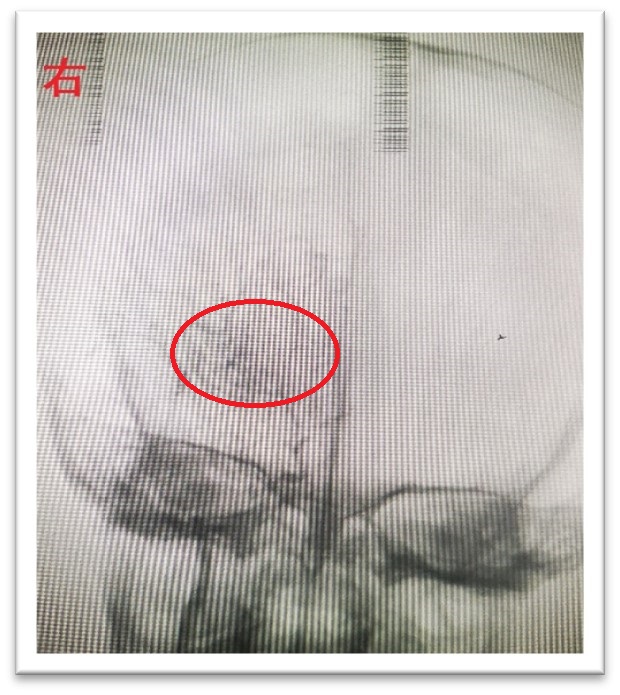

来自江西乐平的馨馨(化名)于5月初突发左下肢无力1天,时常有头晕症状,于是前往江西省儿童医院神经外科就诊,该科主任杨明在了解馨馨病情后,马上办理入院手续,经颅脑磁共振及脑血管成像检查怀疑烟雾病,再次经过评估后为其进行脑血管造影术,可见馨馨左侧脑血管较正常脑血管明显缺如,而右侧可见较为明显烟雾状血管网,确诊馨馨患有双侧烟雾病。